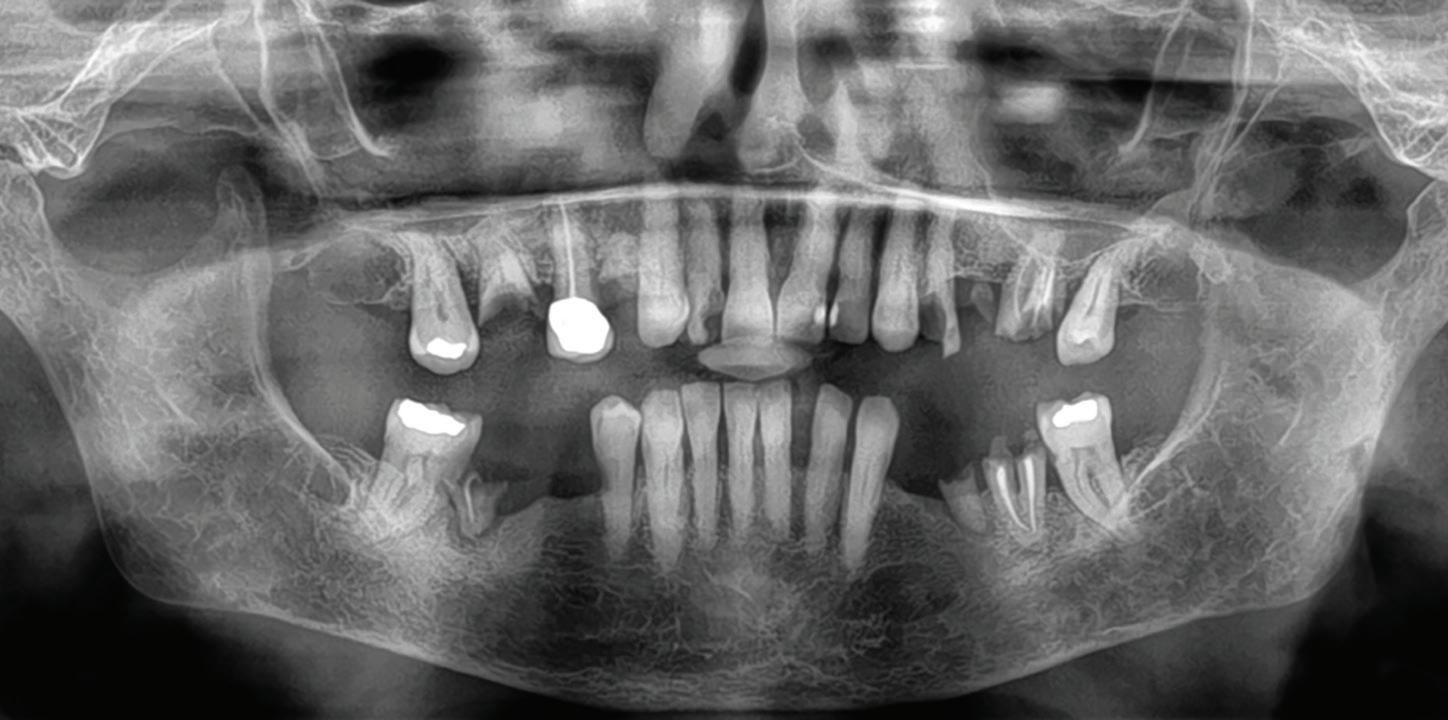

After tooth extraction and socket preservation, patients heal for at least 3 to 4 months. Once the healing process is complete, among the most important procedures for implant planning are cone beam computed tomographic (CBCT) and intraoral scans. The CBCT scan is a 3-dimensional (3D) radiograph that shows the patient’s bone in ways that cannot be seen on 2-dimensional images such as periapical, bitewing, or panoramic radiographs. The use of CBCT scans for implant cases is becoming common because of the important information provided, including bone height, bone width, and the location of arteries, veins, nerves, and other important anatomical features.2

In addition to CBCT scanning, intraoral scanning is helpful. It captures the soft tissue volume so that the clinician can determine the gingival phenotype of the desired implant site as well as the tissue thickness at potential donor sites for connective tissue grafts or free gingival grafts. The intraoral scan can be aligned with the CBCT scan to create an accurate overlay that shows both bone and soft tissue. The anatomical crowns of teeth are the same on the CBCT and intraoral scans, so they can be used as references to align the jaws in the scans.

Fig 1. CBCT images confirm healing of the extraction site after grafting. Fig 2. An occlusal CBCT view reveals the density of the healed graft.